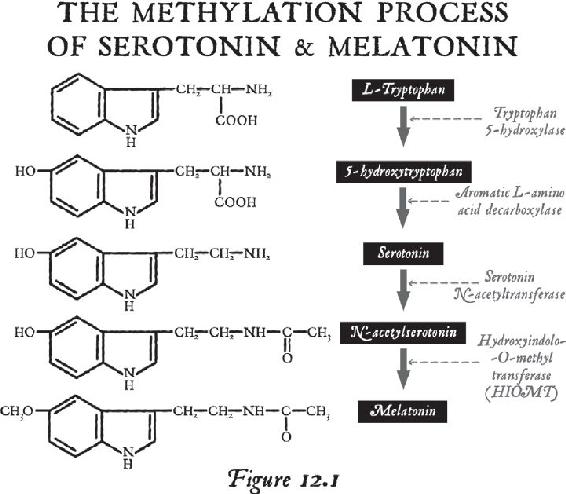

Once you are beyond your associations to this material world and you are in the unified field—chock-full of infinite possibilities—biological systems exist for taking that energy that’s beyond the vibration of matter and turning it into imagery in the brain. That’s where the pineal gland comes in, the subject of Chapter 12. Think of your pineal gland—a tiny gland perched in the central back area of your brain—as an antenna that can transduce frequencies and information and turn them into vivid imagery. When you activate your pineal gland, you are going to have a full-on sensory experience without your senses. That internal event will be more real to you in your mind while your eyes were closed than any past external experience you’ve ever had. In other words, in order to lose yourself fully in the inward experience, it has to be so real that you are there. When this happens, this little gland transmutes melatonin into some very powerful metabolites that cause you to have that type of experience. We will study the properties of this gland and then you will learn how to activate it.